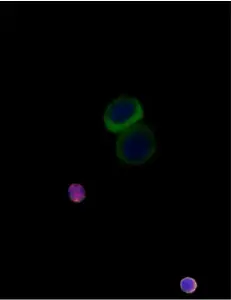

Example images from patient blood samples

Cluster of mesenchymal CTCs - breast